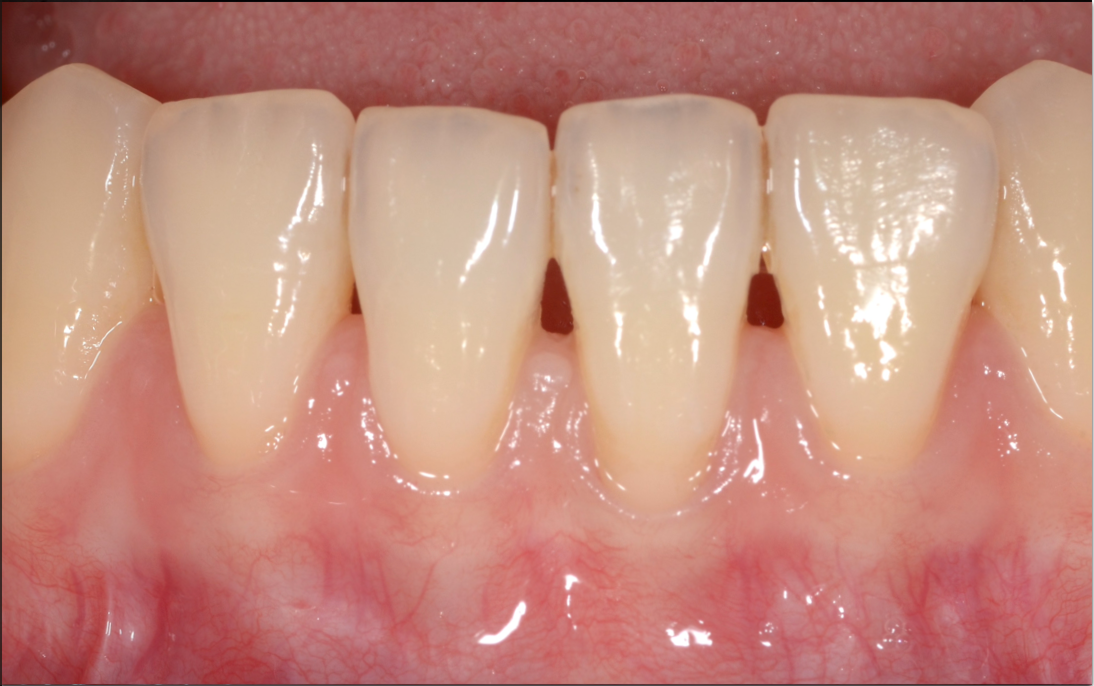

根面被覆術で歯肉退縮を改善した症例

根面被覆術

歯肉が下がって歯根が露出してしまっている箇所に対し、周囲の歯肉を切り開いて寄せるように移動させ、根面に覆い被せる方法です。周囲から移動させるので、手術する部位が1ヵ所で済みます。別箇所からの移植と違って、歯肉の色味の違いがないというメリットがあります。